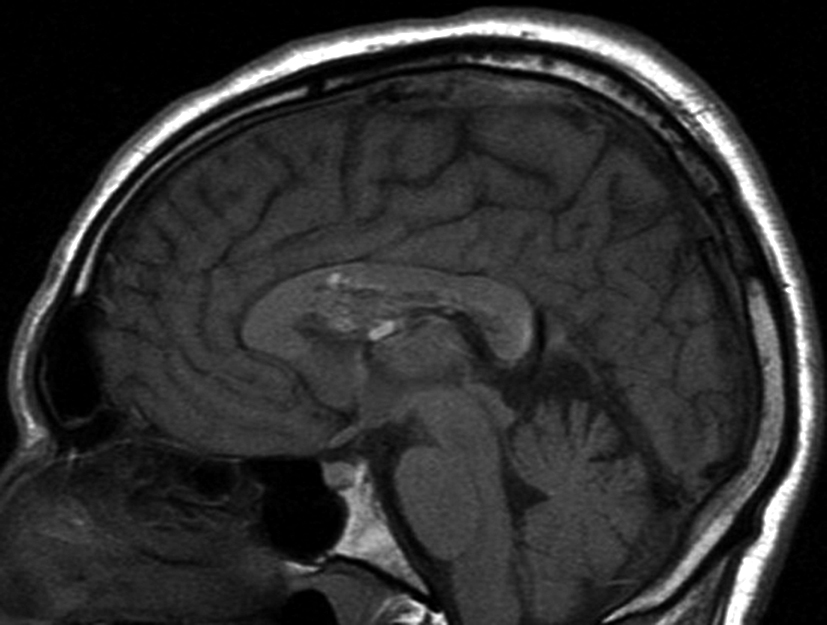

Figura 3

a y b) Imágenes sagitales T1, A. se observa la lesión a nivel del asta frontal de ventrículo lateral derecho y B. se

evidencia la extensión al cuerpo calloso.